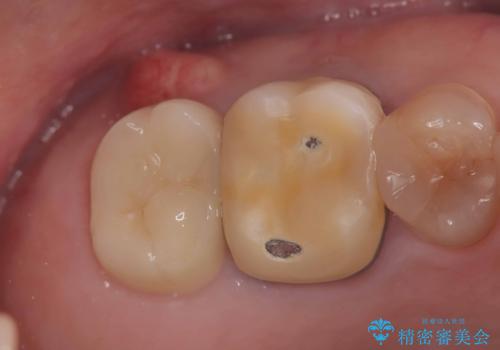

根尖性歯周炎|歯根嚢胞|インプラント治療

- 治療計画

- 右上7番に瘻孔を認め、根管治療を実施しましたが、瘻孔が再発し治癒が得られなかったため、抜歯のうえインプラントによる補綴治療を行いました。

抜歯と歯根嚢胞の除去を行った後、インプラントで治療しました。治療後は「自分の歯のように咬める」と大変ご満足いただけました。